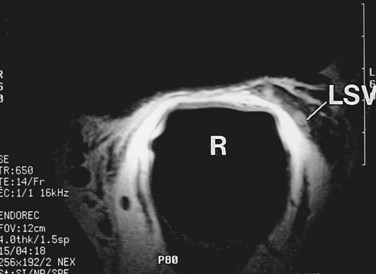

MRI is another useful imaging modality for the seminal vesicles, which gives more anatomic detail than CT. On T2-weighted images, the ampulla of the vas deferens is visible approximately 71% of the time and exhibits low signal intensity. The seminal vesicles exhibit high signal intensity 79% of the time, low signal intensity 19% of the time, and a heterogeneous signal intensity 2% of the time on T2-weighted images (Roy et al, 1993). On T2-weighted images, the seminal vesicles generally have similar or higher intensity than fat in patients less than 70 years of age, and typically have signal intensity lower than that of fat in patients greater than 70 years of age. The convolutions of the seminal vesicles can be seen on T1-weighted imaging with contrast (Fig. 37–20) (Secaf et al, 1991).

Figure 37–20 Transaxial MRI of normal seminal vesicles (SV) with endorectal coli. A, T1-weighted image. B, T2-weighted image. B, bladder; R, rectum.